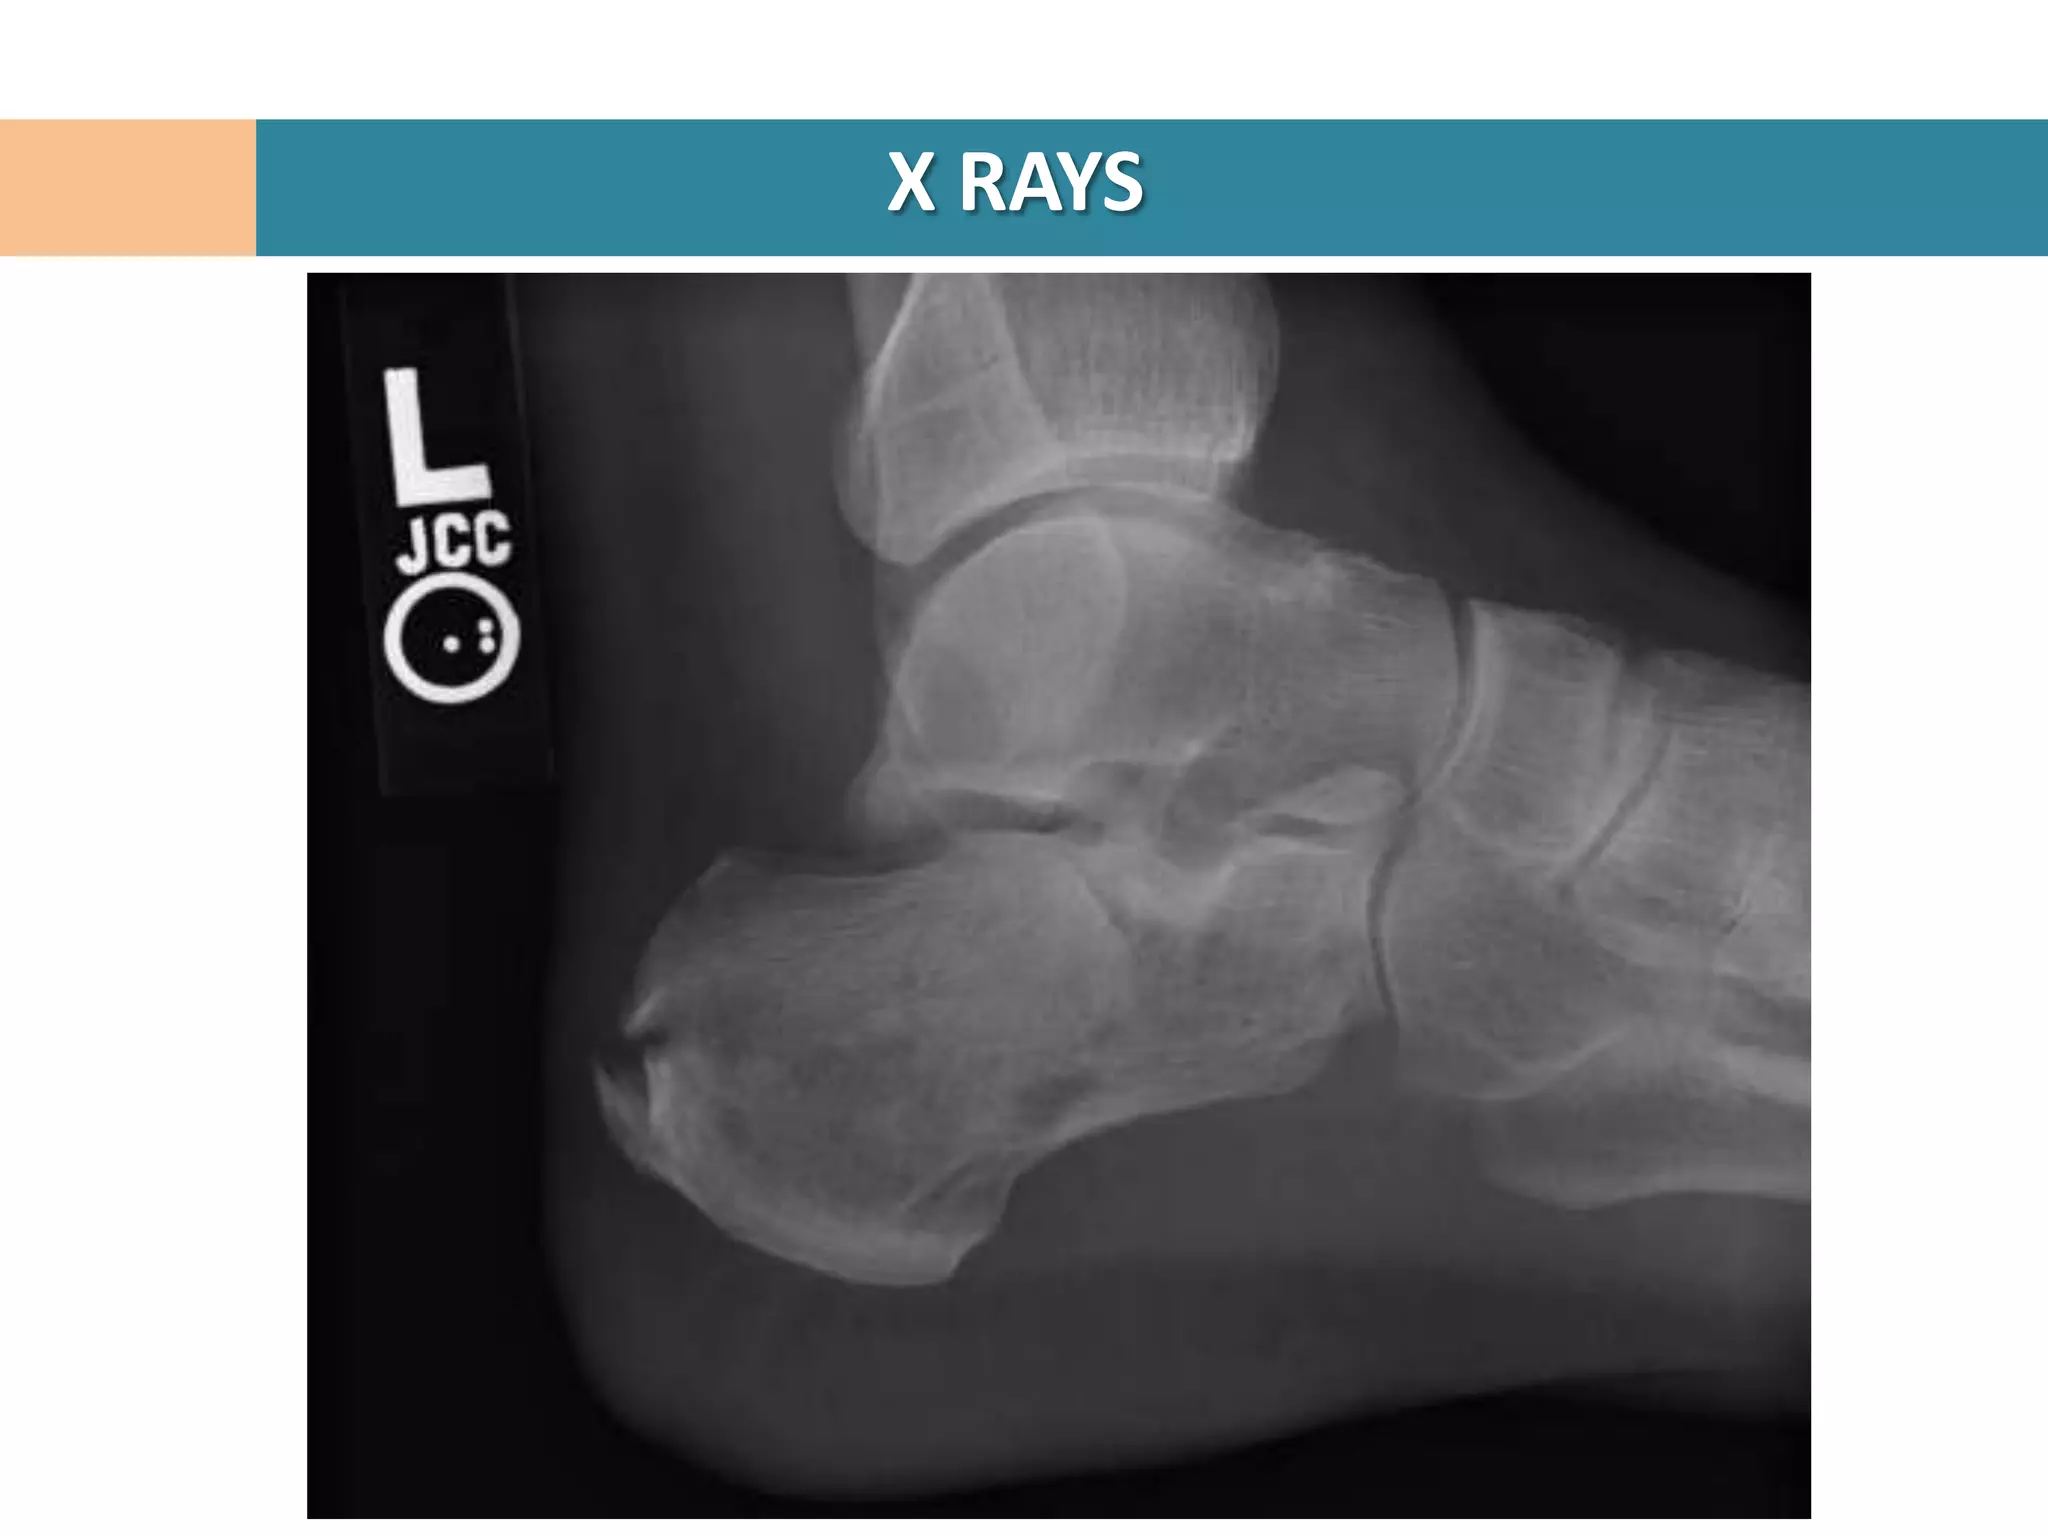

Lateral Hind foot

AP Foot

Harris heel view

Broden’s Views

Ankle AP, Lateral, Mortise

Thoracolumbar spine AP, Lateral

X RAYS

Confirms diagnosis of calcaneal #

Crucial angle of Gissane

Tuber angle of Boehler

Intraarticular #

Loss of ht of post facet

Reduced Boehler angle

Increased Gissane angle

Joint Depression vs Tongue type